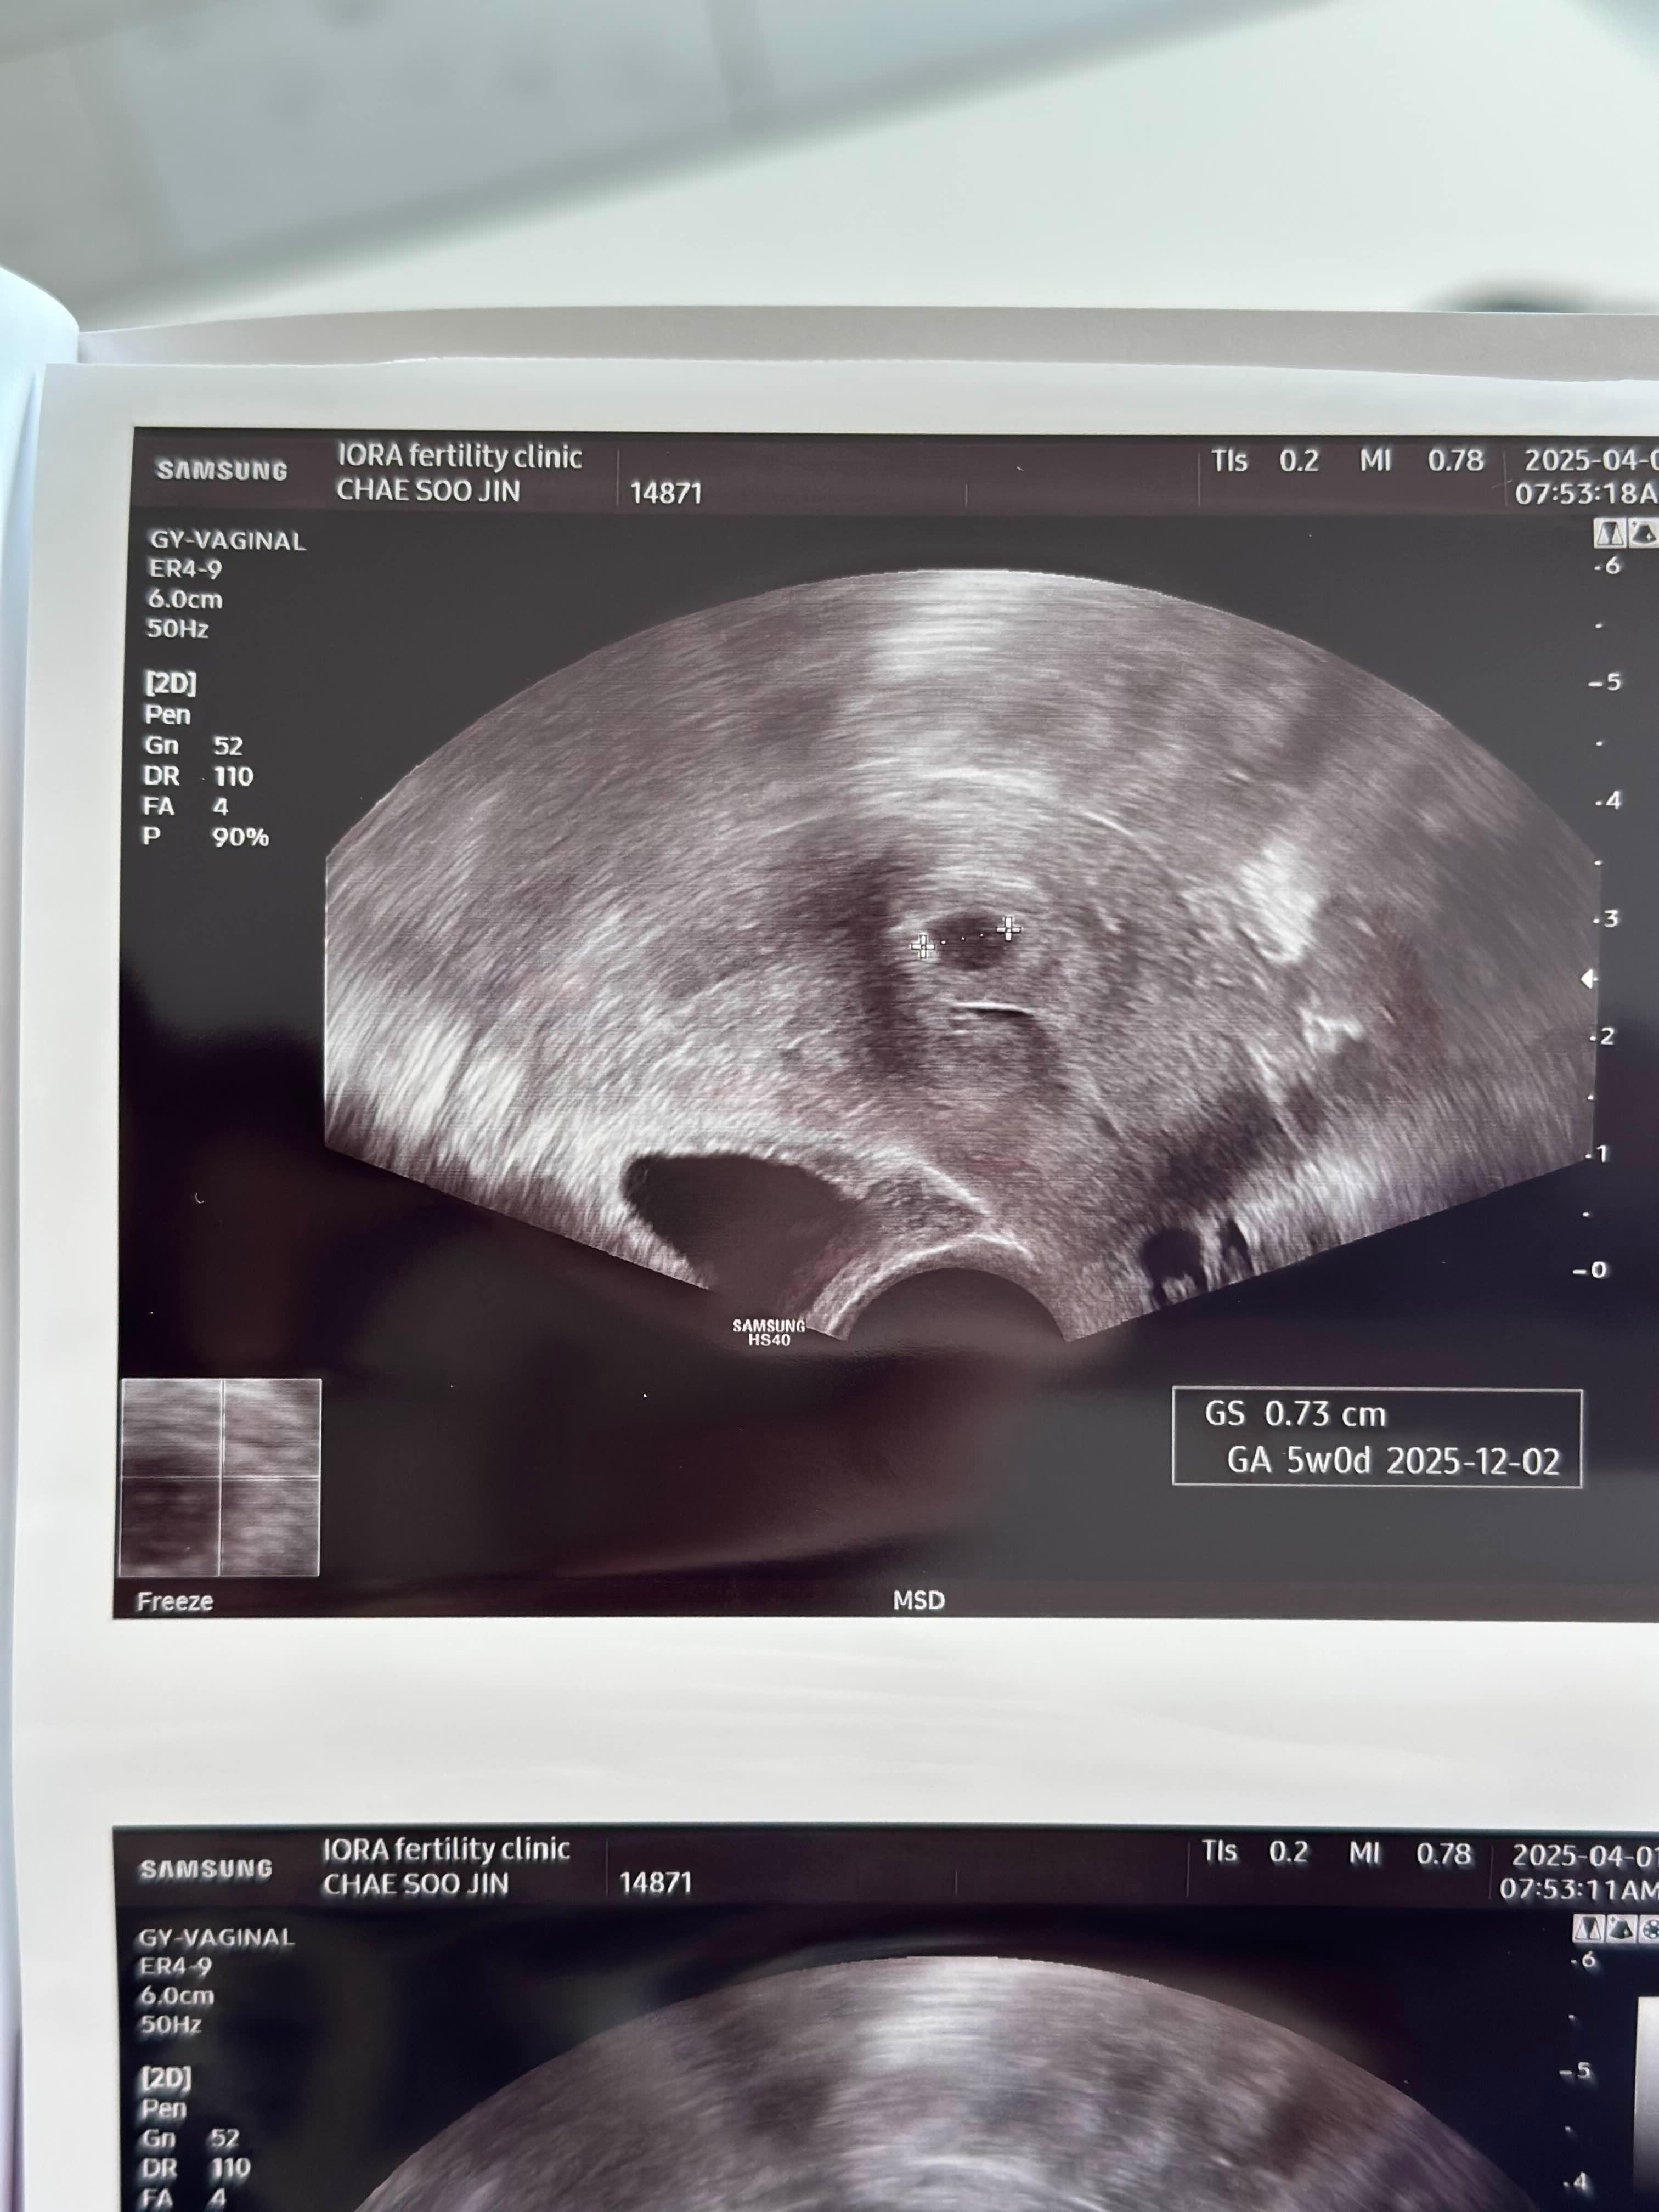

초음파 보자마자 선명하게 보이는 아기집 한 개! 아기집 크기도 0.73cm 로 주수에 알맞게 자랐고, 모양도 동그라니 너무 예쁘게 자리잡았다. 아기집이 보이지 않으면 어쩌나 마음 졸이고 있었는데 아기집을 보고 나니 나도 모르게 눈물이 또르르 났다.

진료가 끝나고 받은 초음파 사진과 산모수첩. 감개무량하다. 사실 아기집을 보고 난 후에는 2차 피검사 수치가 크게 의미가 없다고 한다. 그런데 약 3시간 후 병원에서 전화로 확인한 2차 피검 수치는 10,208점!!! 10배만 오르면 좋겠다 싶었는데 30배 이상 훌쩍 올랐다. 더블링이 확 되면 쌍둥이 확률이 높다던데... 쌍둥이가 될 수도 있을까? 다음주 진료가 더욱 기다려졌다.